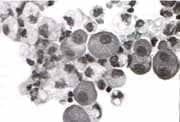

Las células mesoteliales normales (fig 1) son redondas u ovales, con un diámetro entre 7-15 micras, con citoplasma denso, basofílico o anfofílico, de núcleo redondo u oval , generalmente central y con cromatina granular, pudiendo ser observados pequeños nucleolos. Usualmente se encuentran sueltas pero se pueden agrupar en monocapas.

Figura 1. Células mesoteliales normales

Las células mesoteliales reactivas (fig 2) son grandes, redondas u ovales, varían de tamañoalcanzando entre 15-40 micras, su núcleo es redondo y oval, de localización paracentral y poseen macronucléolos, siendo comunes la bi y la multinecleación. Pueden observarse solas o en grupos que asumen la configuración poligonal, o en mosaicos con ventanas entre ellas, que se colorean con PAS y Alcian Blue.

Figura 2. Células mesoteliales reactivas

Las células neoplásicas (fig 3) son grandes, con núcleos que exceden 50 micras de diámetro, con macronucléolos y con una alta relación núcleo-citoplasma.

Figura 3. Células neoplásicas